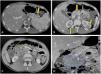

Contrast-enhanced CT scan (CECT) of abdomen revealed a well-defined, hypodense and hypo-enhancing mass lesion of size 5.4 × 6.8 × 6.6 cm in the pancreatic head without any calcification, few non-enhancing necrotic areas within the uncinate process, and dilated pancreatic duct (Figure 1). Smaller similar lesions were also noted in the body and tail of pancreas. An enhancing peri-pancreatic lymph node measuring 2.2 cm was also seen. Bilateral kidneys showed multiple hypo-enhancing lesions, largest measuring 2.8 × 2.5cm at lower pole of right and 2.7 × 2.9 cm at upper pole of left kidney. Liver, spleen, adrenal glands, bowel loops, urinary bladder and vertebrae did not show any focal lesion. Based on the discussed radiological findings a possibility of primary pancreatic lymphoma with bilateral renal deposits was suggested. Following this an ultrasound-guided biopsy from pancreatic mass was performed.

Axial (A, B, C) and coronal (D) contrast enhanced CT scans of abdomen. Well defined hypodense lesions seen in the tail and neck region of pancreas (arrows in ‘A’ and ‘B’) without any obvious evidence of mass effect. Similar lesions are noted at upper pole regions of both the kidneys (arrow in ‘C’).There is a large hypodense mass lesion in upper retroperitoneum with loss of fat planes with head of pancreas (star in ‘C ‘and marked in ‘D’). Patient also had hepatosplenomegaly. Radiological differential of lymphoma likely Non Hodgkin type was suggested.